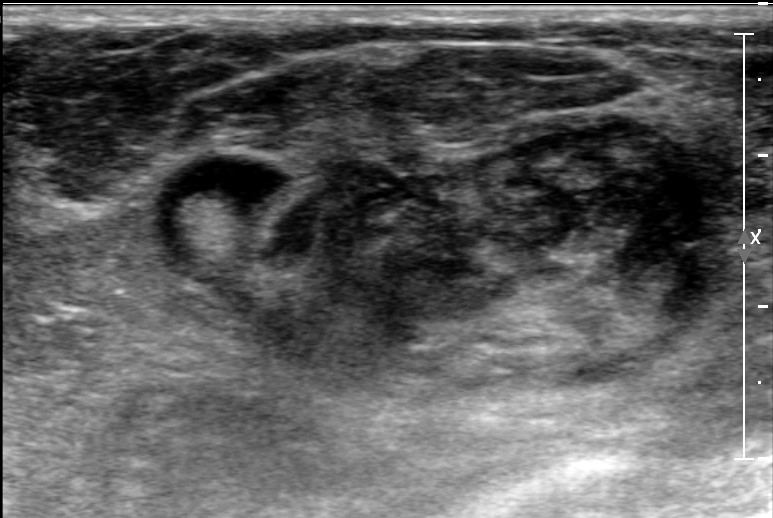

Physical examination revealed a 6.0?×?5.0 cm mass in the left breast. Mammography demonstrated an irregular, fat-containing, heterogeneous mass with circumscribed margins in the upper outer quadrant of left breast. Few scattered foci of coarse calcification were present within the mass. Breast sonography revealed an irregular, parallel, hyperechoic mass with circumscribed margins and no posterior acoustic features in the left breast at 3 o’clock position. Mild vascularity was observed on Color Doppler imaging. Contrast enhanced ultrasound (CEUS) done out of academic interest showed ill-defined, heterogenous enhancing mass, showing irregular shape, having surrounding vessels. Quantitative analysis showed higher PI (pulsatility index), AUC (area under curve) and lower TTP (time to peak) compared to normal tissue. The mass was assessed as Breast Imaging Reporting and Data System category 4b, and ultrasound-guided 14-gauge core biopsy revealed a biphasic tumor composed of bilayered ductal epithelium compressed by the proliferating stroma into leaf like architecture, The stromal cells showed increased cellularity, marked nuclear atypia and pleomorphism with round to oval nuclei, opened up chromatin, prominent nucleoli and moderate to abundant cytoplasm with many bizarre looking tumor giant cells. The stroma showed extensive heterologous lipomatous differentiation composed of neoplastic adipocytes as well as few lipoblasts. Mitosis was 3-4/10/hpf. Final histopathological diagnosis of malignant Phyllodes tumor with liposarcomatous differentiation was given. CT scan chest was done to look for lung metastasis, which revealed an irregular soft tissue mass in left breast with internal focal areas of fat attenuation. No nodules were seen in the lungs. Subsequent lumpectomy was performed and the gross specimen showed a well-demarcated tumor, measuring?6.8?×?6.5 × 3 cm. There were considerable bright yellow fatty components and some cleft-like spaces. Microscopically, the tumor exhibited a typical leaf-like growth pattern with extensive stromal overgrowth and stromal hypercellularity. Extensive areas of lipomatous differentiation were seen ranging from mature adipocytes to lipoblasts showing marked stromal atypia and irregularity. Mitotc activity was 7-8/10hpf. IHC for MDM2 was negative. Overall features were of malignant phyllodes tumor with well differentiated liposarcomatous differentiation.